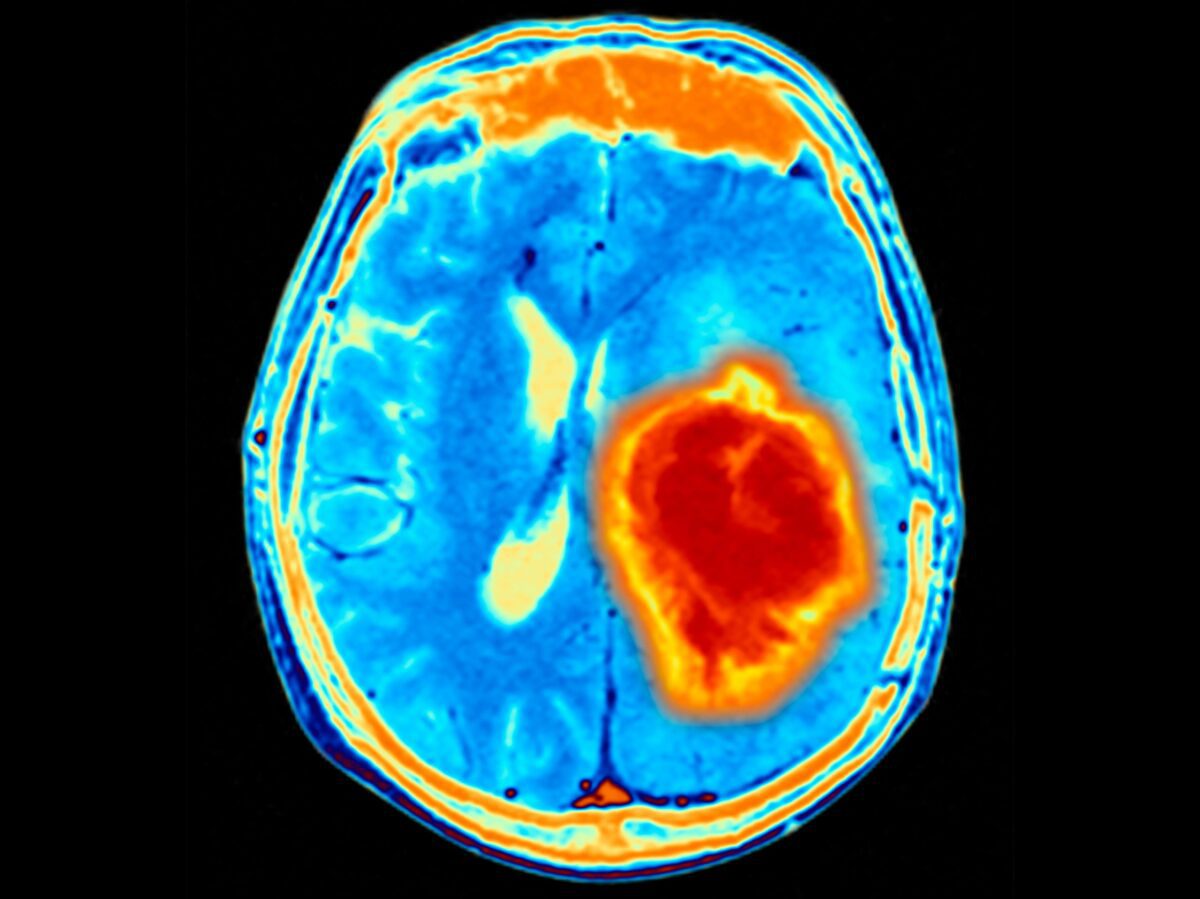

پژوهشگران کشف کردهاند که حلقههای DNA خارج از کروموزوم (ecDNA) ممکن است در آغاز شکلگیری مرگبارترین نوع سرطان مغز (گلیوبلاستوما) نقش داشته باشند.

به گزارش تکناک، این حضور اولیه حلقههای DNA خارج از کروموزوم، توضیحی برای رشد سریع، سازگاری بالا و مقاومت شدید این سرطان در برابر درمانها به حساب میآید. این یافته میتواند راه را برای تشخیص زودهنگام و درمان مؤثرتر این سرطان مغزی خطرناک هموار کند.

گلیوبلاستوما یکی از سختترین انواع سرطان مغز است و بیشتر بیماران مبتلا به آن فقط حدود ۱۴ ماه زنده میمانند. در سالهای اخیر پیشرفت زیادی در درمان آن دیده نشده است و پژوهشگران به دنبال روشهایی هستند تا بتوانند این بیماری را زودتر تشخیص دهند و بهتر درمان کنند.